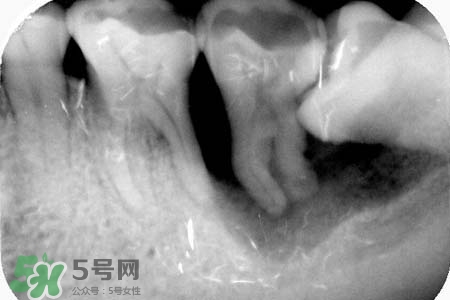

長智齒一般不會引起耳鳴,智齒冠周炎時可能會引起耳部放射性疼痛。耳鳴因素很多,若持續(xù)時間較長,因及時就醫(yī)。如果確定耳朵沒有問題,那么智齒導(dǎo)致的,癥狀是非??赡艿闹驱X阻生,應(yīng)盡早拔除,萌出空間不足、反復(fù)引起發(fā)炎也可考慮拔除。